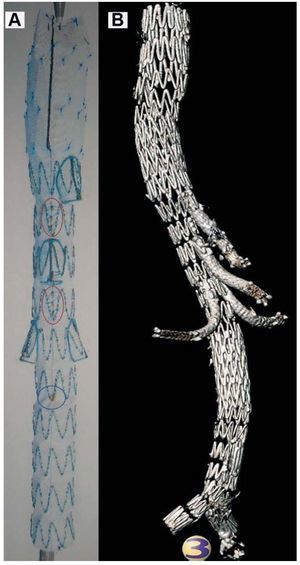

Por abordaje quirúrgico femoral derecho, se implantó un componente cónico torácico (44 ´ 30 ´ 143 mm), seguido del componente toracoabdominal (fig. 1) con las ramas viscerales (tetrarramificada, de 32 ´ 22 ´ 239 mm, para tronco celiaco, arteria mesentérica superior y renales) y de la endoprótesis bifurcada abdominal (24 ´ 20 ´ 171 mm); se utilizó la femoral izquierda para insertar la rama contralateral iliaca (12 ´ 20 ´ 73 mm). Desde un abordaje quirúrgico axilar izquierdo, se completaron las cuatro derivaciones viscerales mediante la aplicación de stents cubiertos de PTFE Fluency® Plus (Bard, Tempe, Arizona), reforzados con respectivos stents descubiertos Luminexx® (Bard) para evitar angulaciones.

Fig. 1. Prótesis toracoabdominal ramificada personalizada. A: detalle del segmento que comprende las cuatro ramas viscerales. B: reconstrucción tridimensional posquirúrgica de todos los componentes.